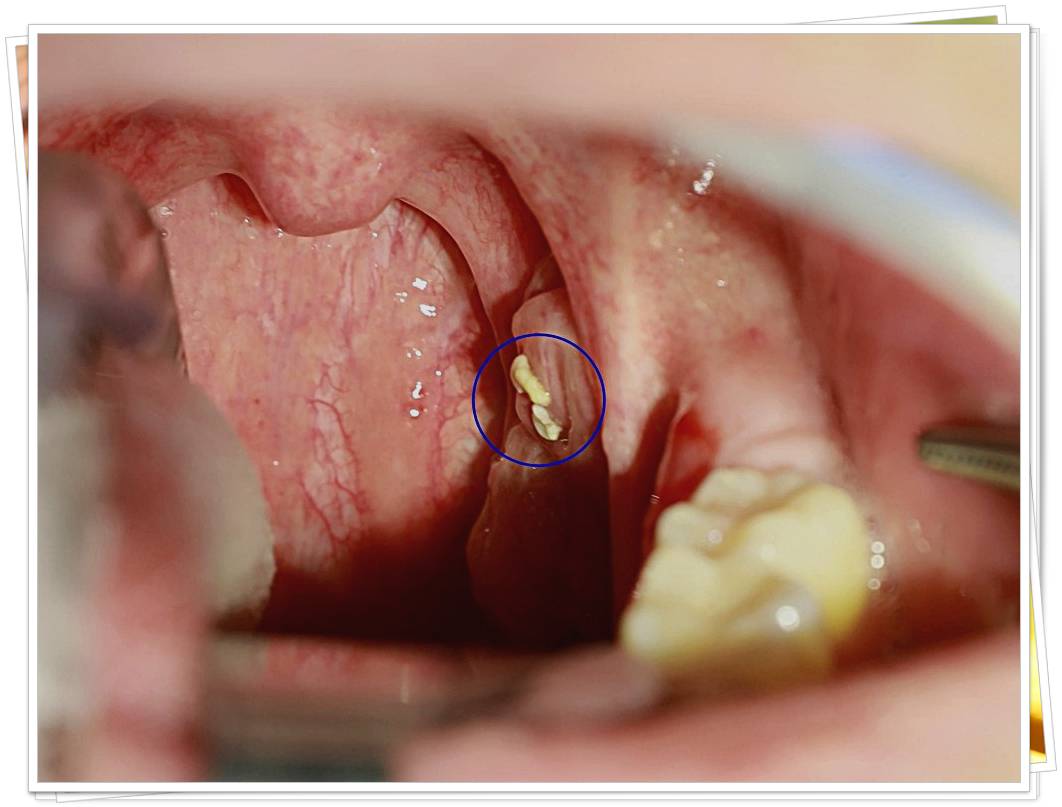

- 편도 부위의 흰색·노란색 알갱이

- 거울로 목 안쪽을 비춰봤을 때 작은 결석이 보인다.

- 목에서 특이한 냄새 덩어리 배출 경험

- 기침하거나 음식 먹다 작은 돌처럼 생긴 알갱이가 나온 적이 있다.